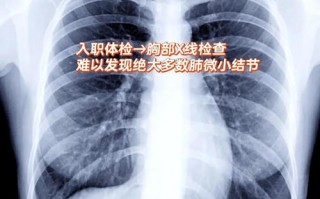

AI读片肺结节过度诊断怎么办?

您提出的“人工智能读片肺结节过度”是一个非常精准且关键的问题,是当前AI在医疗影像领域应用中最受关注的挑战之一,这里的“过度”可以从两个层面来理解:技术层面:假阳性(False Positive)过高...